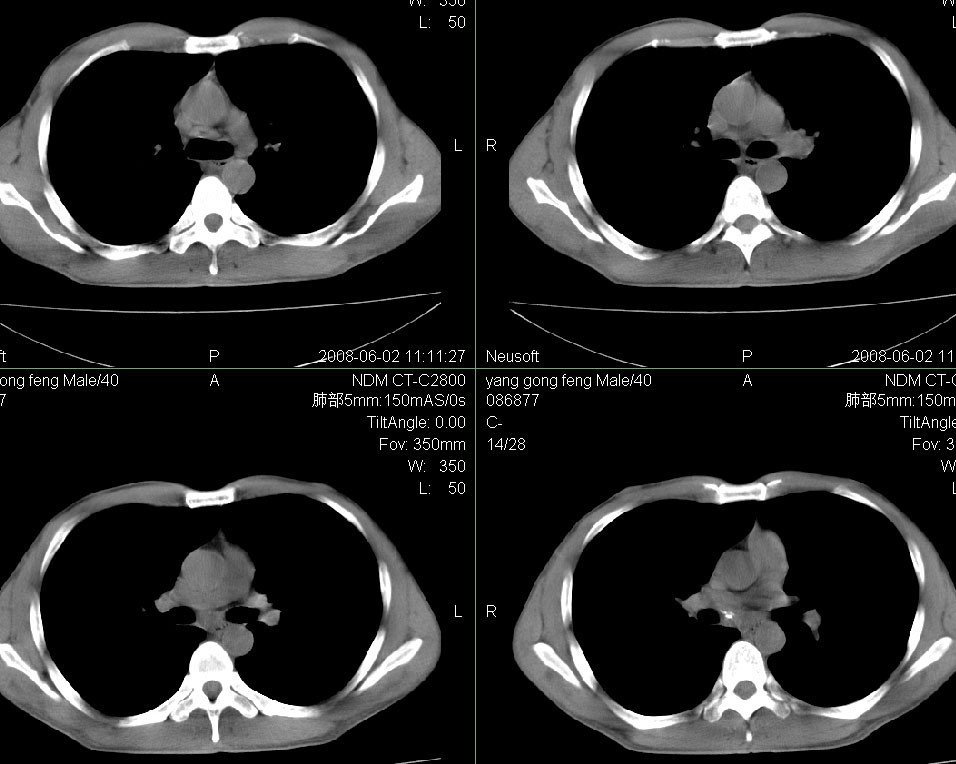

标题: CT15138:男,40,咳嗽胸痛. [打印本页]

标题: CT15138:男,40,咳嗽胸痛.

外院穿刺未见癌细泡,结核菌素实验阳性,未正规治疗2个月复查病灶及纵隔淋巴结增大

结合病史及临床表现考虑右侧中心型肺癌纵隔转移,

右侧中心型肺癌纵隔转移!

右肺中叶肺癌,纵隔淋巴结转移.

右侧中心型肺癌纵隔转移